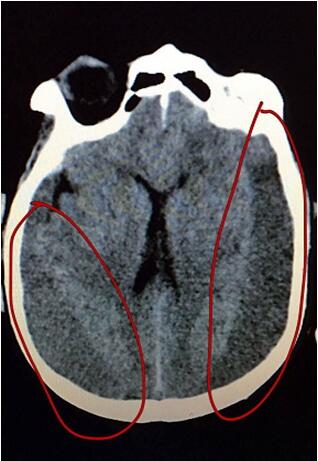

患者在外院行頭顱MRI提示雙側(cè)額顳慢性硬膜下血腫并積液,主管醫(yī)生段威和宋俊杰副主任醫(yī)師仔細(xì)看了片子后,發(fā)現(xiàn)雙側(cè)硬膜下出血高達(dá)100ml??紤]到患者年齡大,開顱手術(shù)相對(duì)風(fēng)險(xiǎn)大,遂決定暫采取血腫腔鉆孔引流的方式。家屬了解病情后焦灼不已,宋醫(yī)生和段醫(yī)生迎難而上,為患者進(jìn)行了全面的檢查與評(píng)估。經(jīng)過細(xì)致的術(shù)前討論及充分的術(shù)前準(zhǔn)備,10月26日,醫(yī)生為患者在局麻下行雙側(cè)額顳慢性硬膜下血腫鉆孔引流術(shù),手術(shù)順利完成。